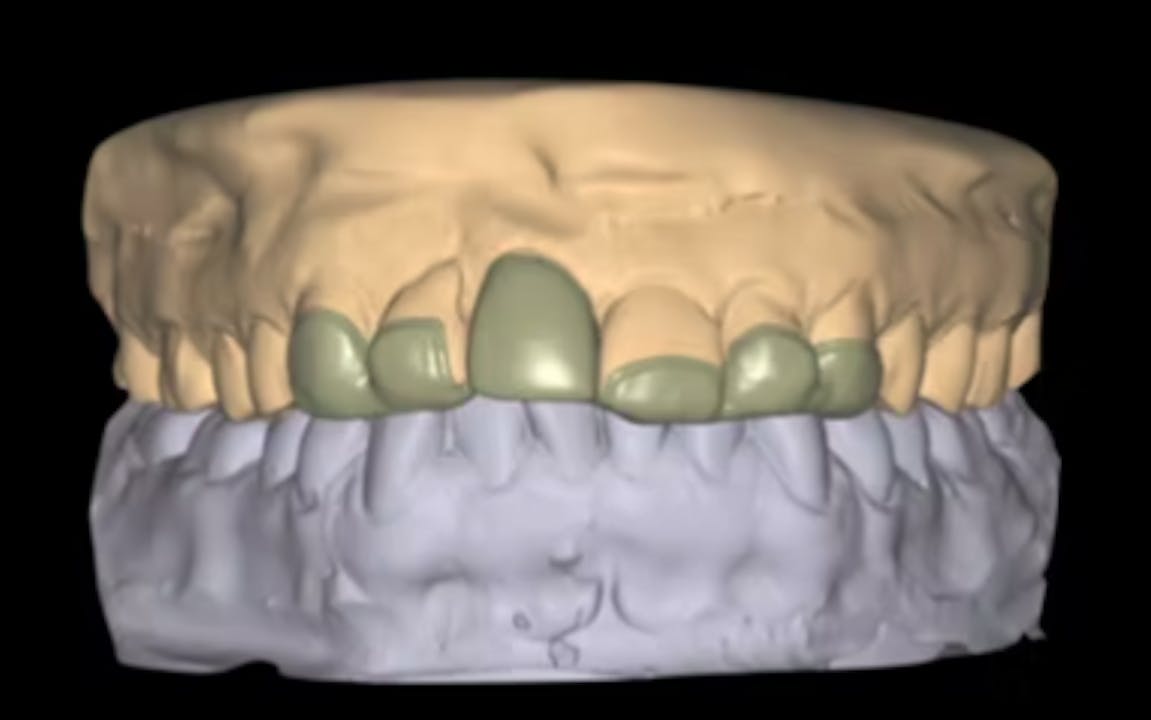

CLINICAL VIDEO Implant placement with digital planning, hard and soft Gide Dental Reviews Gide dental institute, los angeles, california. • 550+ clinical videos on web and app • new dental videos added. Clinical videos, expert interviews, live broadcasts over. Dive deep (at your own pace) in a comprehensive online master class or residency with topics covering implant dentistry, esthetic dentistry,. Read 26 customer reviews of gide dental center, one of the best. Evidence. Gide Dental Reviews.